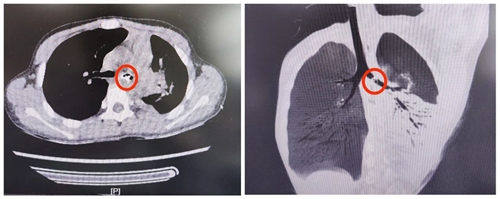

強(qiáng)強(qiáng)非常害怕,回家后也不敢將情況告知父母。接下來的8天中,家長(zhǎng)發(fā)現(xiàn)孩子總是時(shí)不時(shí)咳嗽,而且伴隨發(fā)熱,隨后家長(zhǎng)帶著孩子在當(dāng)?shù)蒯t(yī)院就診,胸部CT檢查中發(fā)現(xiàn)氣管中竟有一異物,且伴隨肺不張及肺炎,反復(fù)追問下強(qiáng)強(qiáng)才終于說了實(shí)話。父母焦急萬(wàn)分,趕忙帶孩子來到青島婦女兒童醫(yī)院耳鼻喉科就醫(yī)。

接診醫(yī)生立即開通綠色通道,將患兒收治入院。緊急完善相關(guān)手術(shù)評(píng)估后,進(jìn)行手術(shù)。手術(shù)團(tuán)隊(duì)利用纖維支氣管鏡,發(fā)現(xiàn)有一個(gè)銀色金屬樣物將左側(cè)支氣管完全阻塞,并且異物的部分邊緣嵌入了氣管壁黏膜。手術(shù)團(tuán)隊(duì)精密操作,將異物邊緣與黏膜壁進(jìn)行了仔細(xì)松解分離,并利用異物鉗將異物完整取出。當(dāng)異物取出后,患兒左側(cè)支氣管內(nèi)涌出大量黃色膿性分泌物……